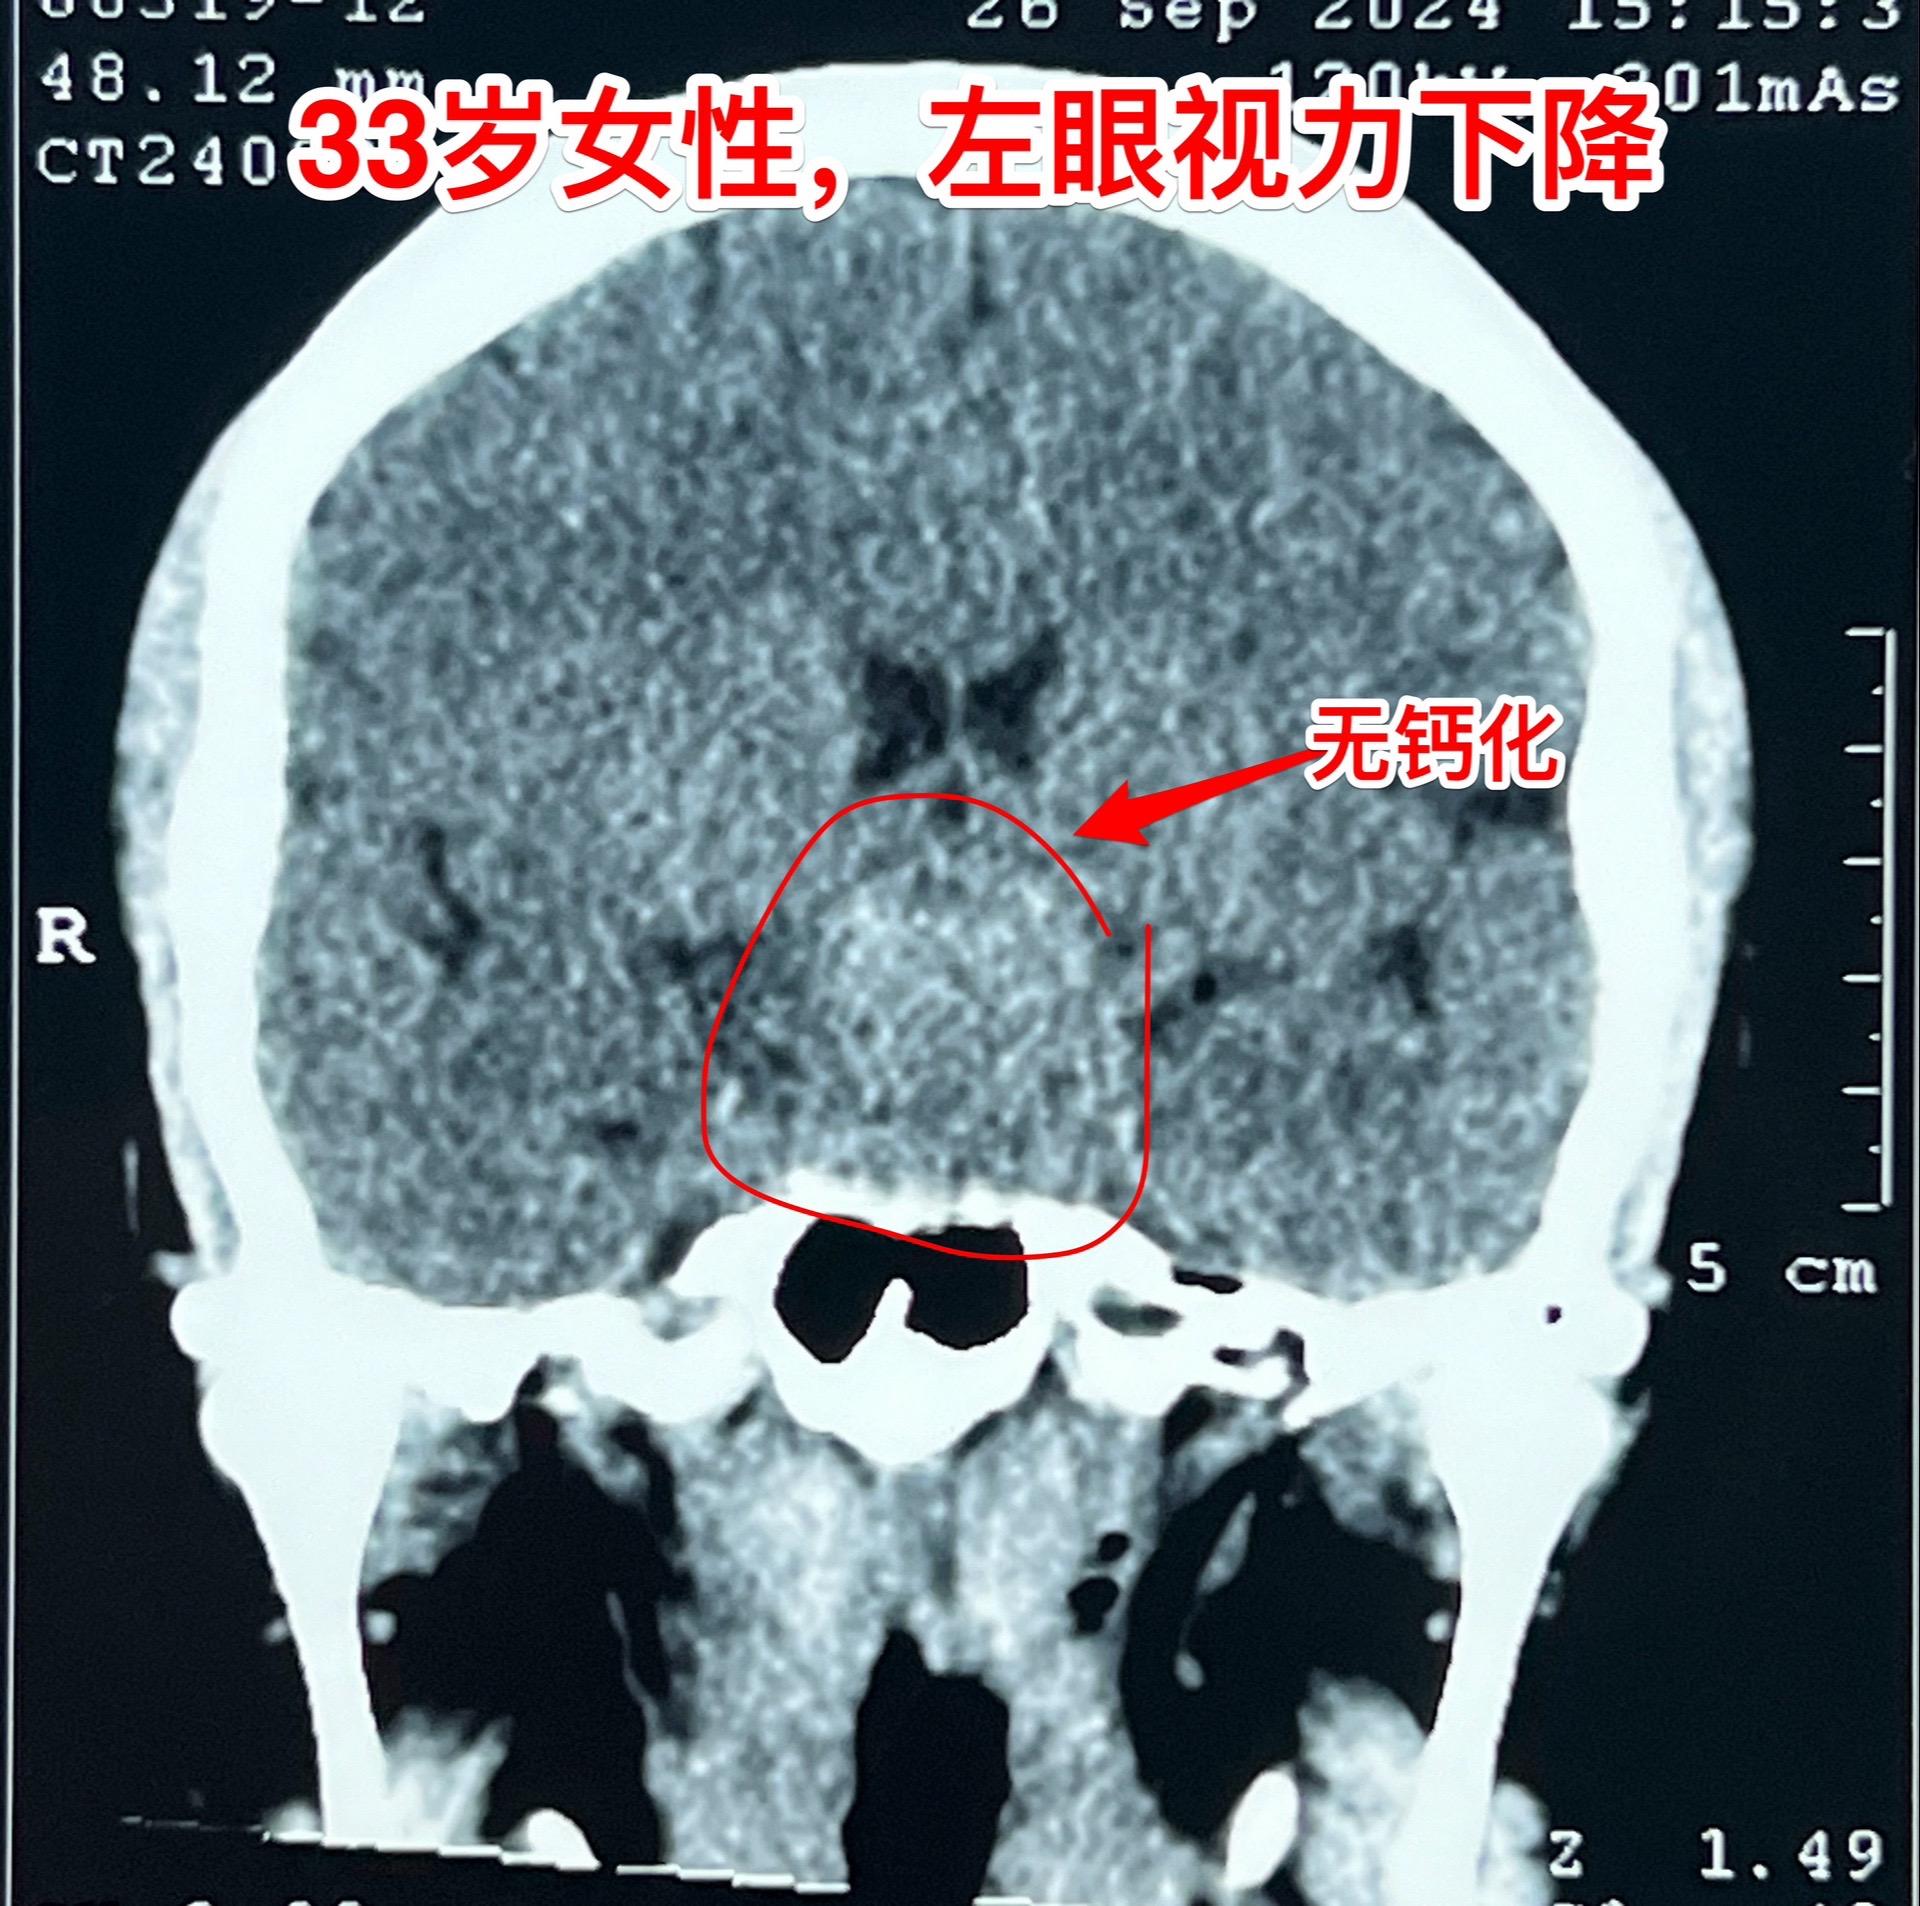

国庆节长假后第一天完成两个手术。一个手是33岁女性,来自云南省香格里拉。因左眼视力下降,到医院检查发现鞍区肿瘤,怀疑是颅咽管瘤。病人没有内分泌功能障碍。影像学上肿瘤是实性的,没有钙化,而且可以看见垂体信号。到底是什么肿瘤呢?今天手术中取肿瘤标本作快速冰冻病理检查,报告是垂体瘤。肿瘤得到完全切除,手术后病人视力好转了。 另一个手术是11岁男孩子,颅咽管瘤复发。经原切口翼点入路将肿瘤完全切除。术前磁共振只看见一个圆形肿瘤,术中发现除了这个肿瘤外还有5个散在的钙化斑,均得到完全切除。这样的散在钙化斑是潜在的危险因